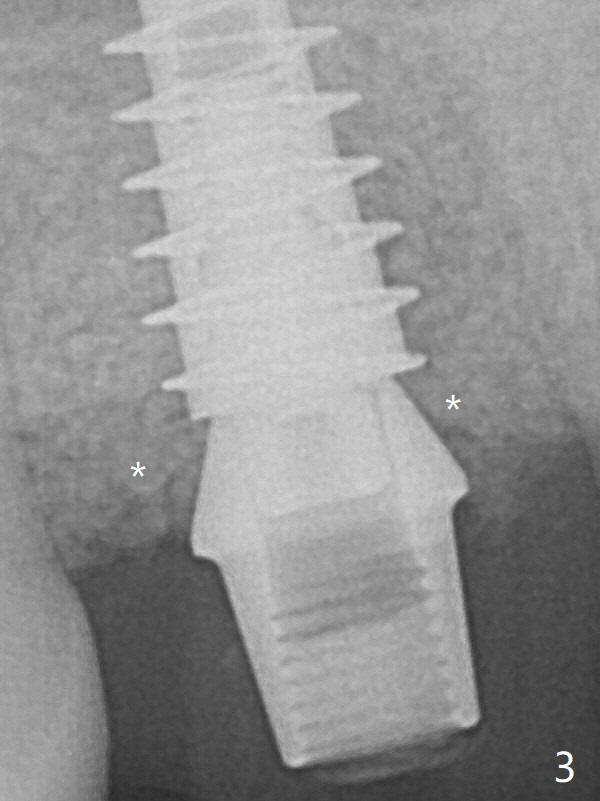

Then a 5x4(2) mm pair abutment is placed, followed by the third round of bone graft (Fig.3 *).  Finally an immediate provisional is fabricated to keep the graft in place.  The 2nd round of the bone graft should be apical to the implant plateau (to prevent the graft from getting into the implant well), whereas the 3rd round of it covers the remaining implant surface to reduce the possibility of future periimplantitis.